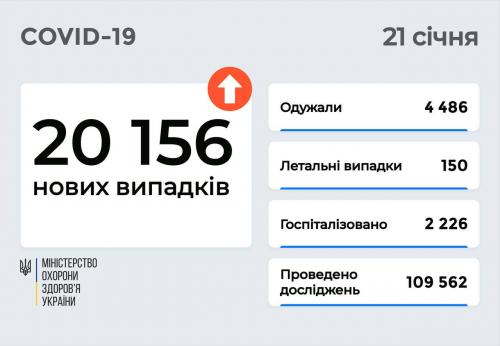

МОЗ: Уперше з початку пандемії було зроблено понад 100 тисяч ПЛР-досліджень за добу